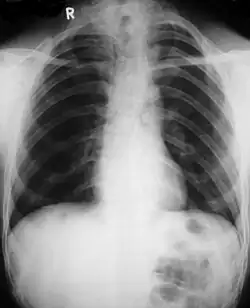

Different features of the dysostosis are significant. Radiological imaging helps confirm the diagnosis. During gestation (pregnancy), clavicular size can be calculated using available nomograms. Wormian bones can sometimes be observed in the skull.[20]